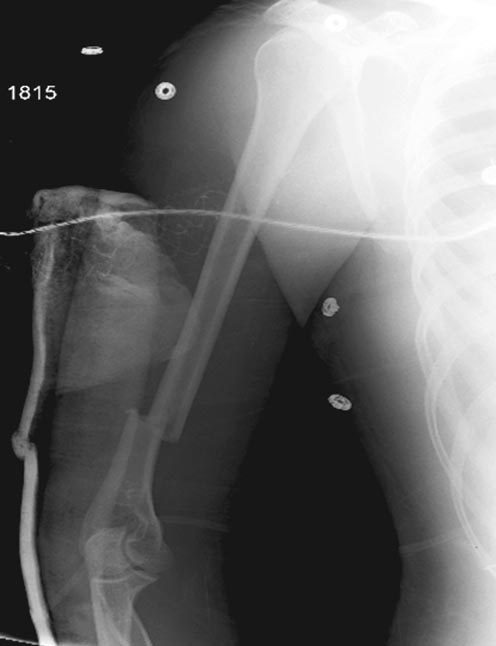

Раны в области коленного сустава и на плече до сих пор чистые, остаются

открытыми. Отсутствует признаки инфекции, решили превратить недостаток в

преимущество, т.е. фиксировать через открытые раны пластинами.

На 11й день фиксация плеча также пластиной.